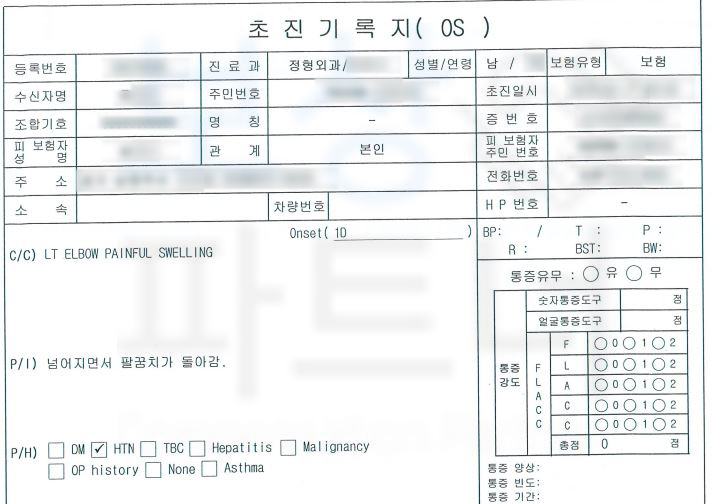

문제는 수술이 잘 마무리 되었어도 재활 치료를 통해 팔꿈치 관절의 가동범위를 늘리고 회복하는 과정이 필요하죠. 보상파트너에 문의하신 유@@님은 공장에 출입하시던 중 미끄러지는 사고를 당해 팔꿈치골절 진단을 받게 되었습니다.

진단서를 보시면

척골 갈고리돌기 의 골절 S52030 팔꿈치골절 진단을 받으셨고 금속 고정술을 시행하셨습니다.